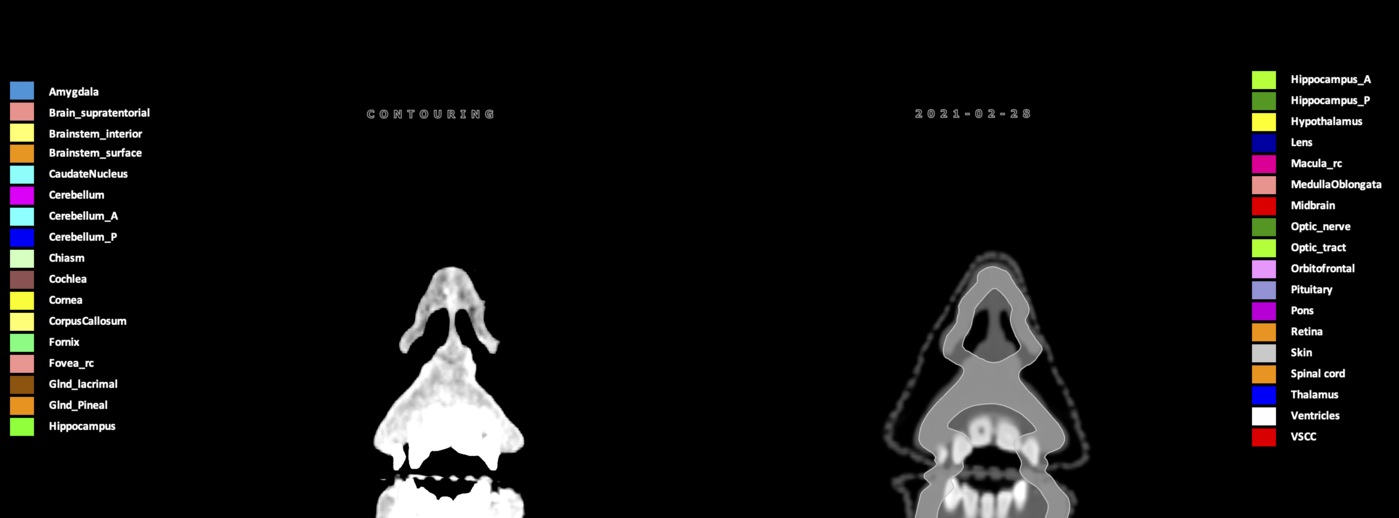

Included are all OARs known to be relevant for radiation-induced toxicity in neuro-oncology: brain, brainstem (midbrain, pons, medulla oblongata), chiasm, cerebellum (anterior & posterior), cochlea, cornea, hippocampus (anterior & posterior), hypothalamus, lens, lacrimal gland, optic nerve, pituitary, skin, and vestibular & semicircular canals. To further facilitate research on cognition, vision and radiological changes after irradiation of the brain, potential clinically-relevant OARs are included: amygdala, caudate nucleus, cerebellum (anterior & posterior), corpus callosum, fornix, macula, optic tract, orbitofrontal cortex, periventricular space (PVS), pineal gland, and thalamus.

Three-dimensional delineation of the 25 consensus OARs for neuro-oncology are shown on CT (WW/WL 120/40, 3000/600), 3T MR images, (T1Gd, T2FLAIR 1mm) and 7T MR (MP2RAGE 0.7 mm). All are presented in transversal, sagittal and coronal view.